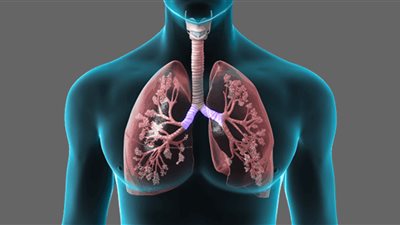

علاج انتفاخ الرئة الحاد.. يبحث العديد من الأشخاص عن علاج انتفاخ الرئة الحاد الذي يتسبب في الإصابة بالانسداد الرئوي المزمن وهو عبارة عن مرض رئوي التهابي مزمن ينتج عنه إعاقة تدفق الهواء الخارج من الرئتين؛ لذا سنتعرف خلال هذا التقرير على علاج انتفاخ الرئة الحاد.

وعن علاج انتفاخ الرئة الحاد، يذكر الدكتور عمر علاء الدين عطا، استشاري ومدرس جراحة القلب والصدر، أن الكثير من الأشخاص المصابين بمرض الانسداد الرئوي المزمن يعانون أشكالًا خفيفة من هذا الداء التي قد تتطلب تناول بعض العلاجات القليلة مع الإقلاع عن التدخين، لافتًا إلى أنه حتى خلال المراحل الأكثر تقدمًا من هذا الداء، يمكن تناول علاج فعال يمكنه التحكم فبلأعراض، وإبطاء تفاقم المرض، وكذلك تقليل احتمالية حدوث مضاعفاته الغير مرغوبة، بجانب تحسين قدرة المريض على التمتع بحياة أفضل.

ويشير إلى أن الجراحة تعد أحد الخيارات المتاحة لدى بعض الأشخاص المصابين ببعض أشكال انتفاخ الرئة الحاد، وخاصة الذين لا تساعدهم الأدوية فقط في الشفاء بشكل كافٍ، مشيرًا إلى أن الحلول الجراحية عادة ما تشتمل على ما يلي:

- إجراء جراحة تصغير حجم الرئة.

- أو أيضًا يمكن استئصال الفقاعات الرئوية.

ويشير استشاري ومدرس جراحة القلب والصدر، إلى أن أعراض انتفاخ الرئة متعددة وعادة ما تتضمن ما يلي:

- وجود صعوبة في التنفس.

- وأيضًا السعال.

- فضلًا عن تكوُّن المخاط أو البلغم.

- بجانب خروج صوت الأزيز.

أسباب الإصابة بانتفاخ الرئة الحاد

وعن أسباب الإصابة بانتفاخ الرئة الحاد، ينبه الدكتور عمر علاء الدين عطا، إلى أن لإصابة بهذا المرض عادة ما تحدث نتيجة التعرض لفترات طويلة للغازات أوالجسيمات المهيجة، التي قد تنبعث في أغلب الحالات من دخان السجائر.

انتفاخ الرئة هل هو خطير؟

وللإجابة على سؤال انتفاخ الرئة هل هو خطير؟، يلفت استشاري ومدرس جراحة القلب والصدر، الانتباه إلى أن الأشخاص المصابين بمرض الانسداد الرئوي المزمن أو انتفاخ الرئة عادة ما يكونون أكثر عرضة لخطورة الإصابة بمرض القلب وأيضًا سرطان الرئة والعديد من لحالات المرضية الأخرى.

هل يمكن الشفاء من مرض تورم الرئة؟

ولمن يرغب في معرفة إجابة سؤال هل يمكن الشفاء من مرض تورم الرئة؟، يقول الدكتور عمر علاء الدين عطا: لا يمكن الشفاء التام من انتفاخ الرئة ومرض الانسداد الرئوي المزمن، ولكن قد تساعد بعض العلاجات كما ذكرنا أعلاه في تخفيف أعراض المرض وإبطاء تطوره وتفاقم أعرضه.